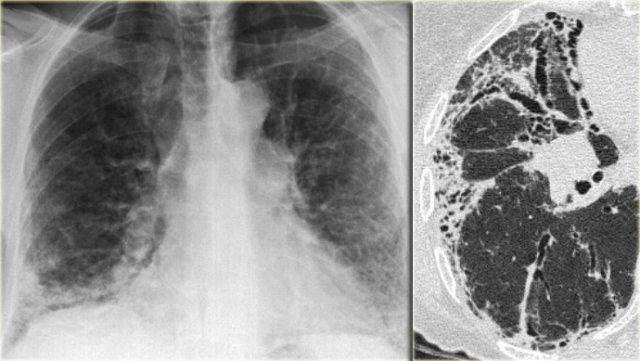

Phim X-quang ngực bên trái cho thấy các vùng đông đặc khoang khí dạng nốt lan tỏa.

HRCT chứng minh nhiều nốt phân bố quanh phế quản, một phần hợp lưu, và một ổ tạo hang ở phổi phải, gợi ý mạnh cho chẩn đoán lao phổi.

Các bệnh lý khác trong chẩn đoán phân biệt bao gồm u hạt Wegener hoặc ác tính (cả hai đều không có hình ảnh “cành cây nảy chồi”).

Bên trái là phim X-quang ngực của bệnh nhân 19 tuổi mắc mô bào tế bào Langerhans.

Dấu hiệu nổi bật trên phim X-quang ngực là hình ảnh lưới và đó là giới hạn có thể nhận định được.

Ngoài ra còn có hình ảnh ứ khí phổi.

Không thể nhận ra rằng hình ảnh này được gây ra bởi nhiều nang.